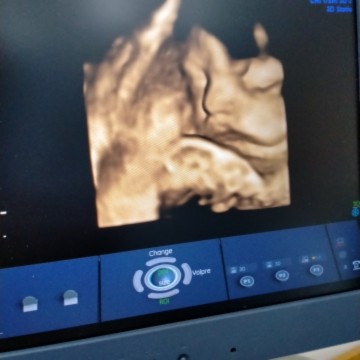

ลูกสาว

มาอวดภาพอันตราซาวด์ลูกๆที่เกิดเดือน พ.ค หน่อยจร้ ทีมพฤษภาคม❤️❤️

กำหนด25 พ.ค.63 นี้ค่ะ ยังเงียบอยู่เลย

กำหนดผ่า 25 พ.ค. นี้แล้วจ้า น้องณิชา

ลูกสาว 37W แล้วค่ะ

จมูกโด่งมากแม่

ดั้งโด่งง